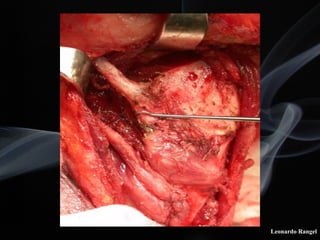

!TÉCNICA

LPSC

Leonardo Rangel

Articulação crico-tireóidea

! A incisão de abertura superior da laringe deve

ser exatamente ao nível do pecíolo.

! No lado do tumor, a mucosa subglótica ao nível

da cricóide, deve ser descolada juntamente com

o pericôndrio interno.

! É necessário a preservação do nervo laríngeo

(recorrente) e de uma aritenóide no lado

normal.

! A aproximação da cartilagem cricóide ao osso

hióide deve ser efetuada num mesmo nível.